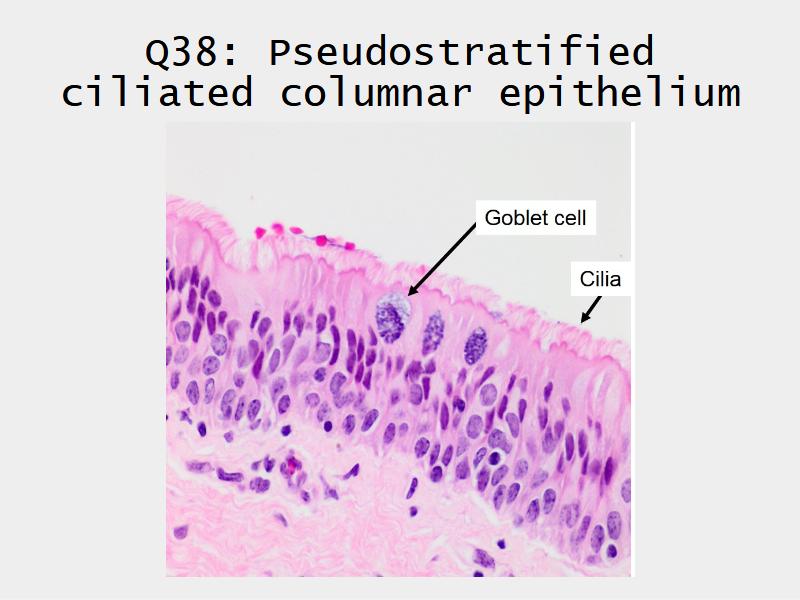

Respiratory epithelium

- Pseudostratified

- Ciliated

- Columnar

- Epithelium with

- 4 Cells

- Ciliated columnar cells

- Non-ciliated columnar cells

- Goblet cells

- Basal cells